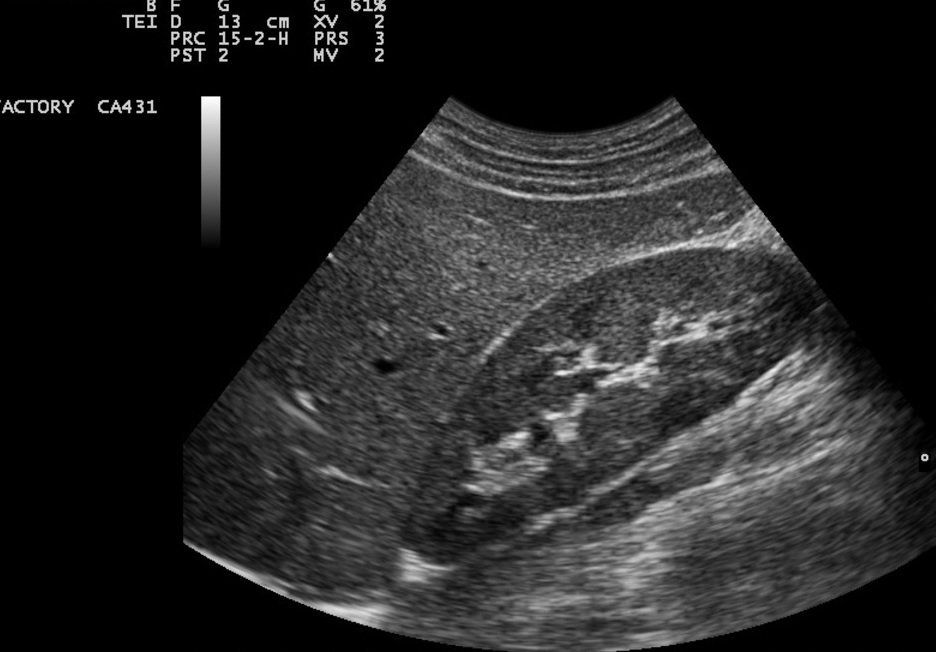

Exploración de riñón, uréter y vejiga

Una investigación detallada para observar el tamaño, el carácter y la forma de los riñones, el uréter, la vejiga llena y la vejiga vacía.